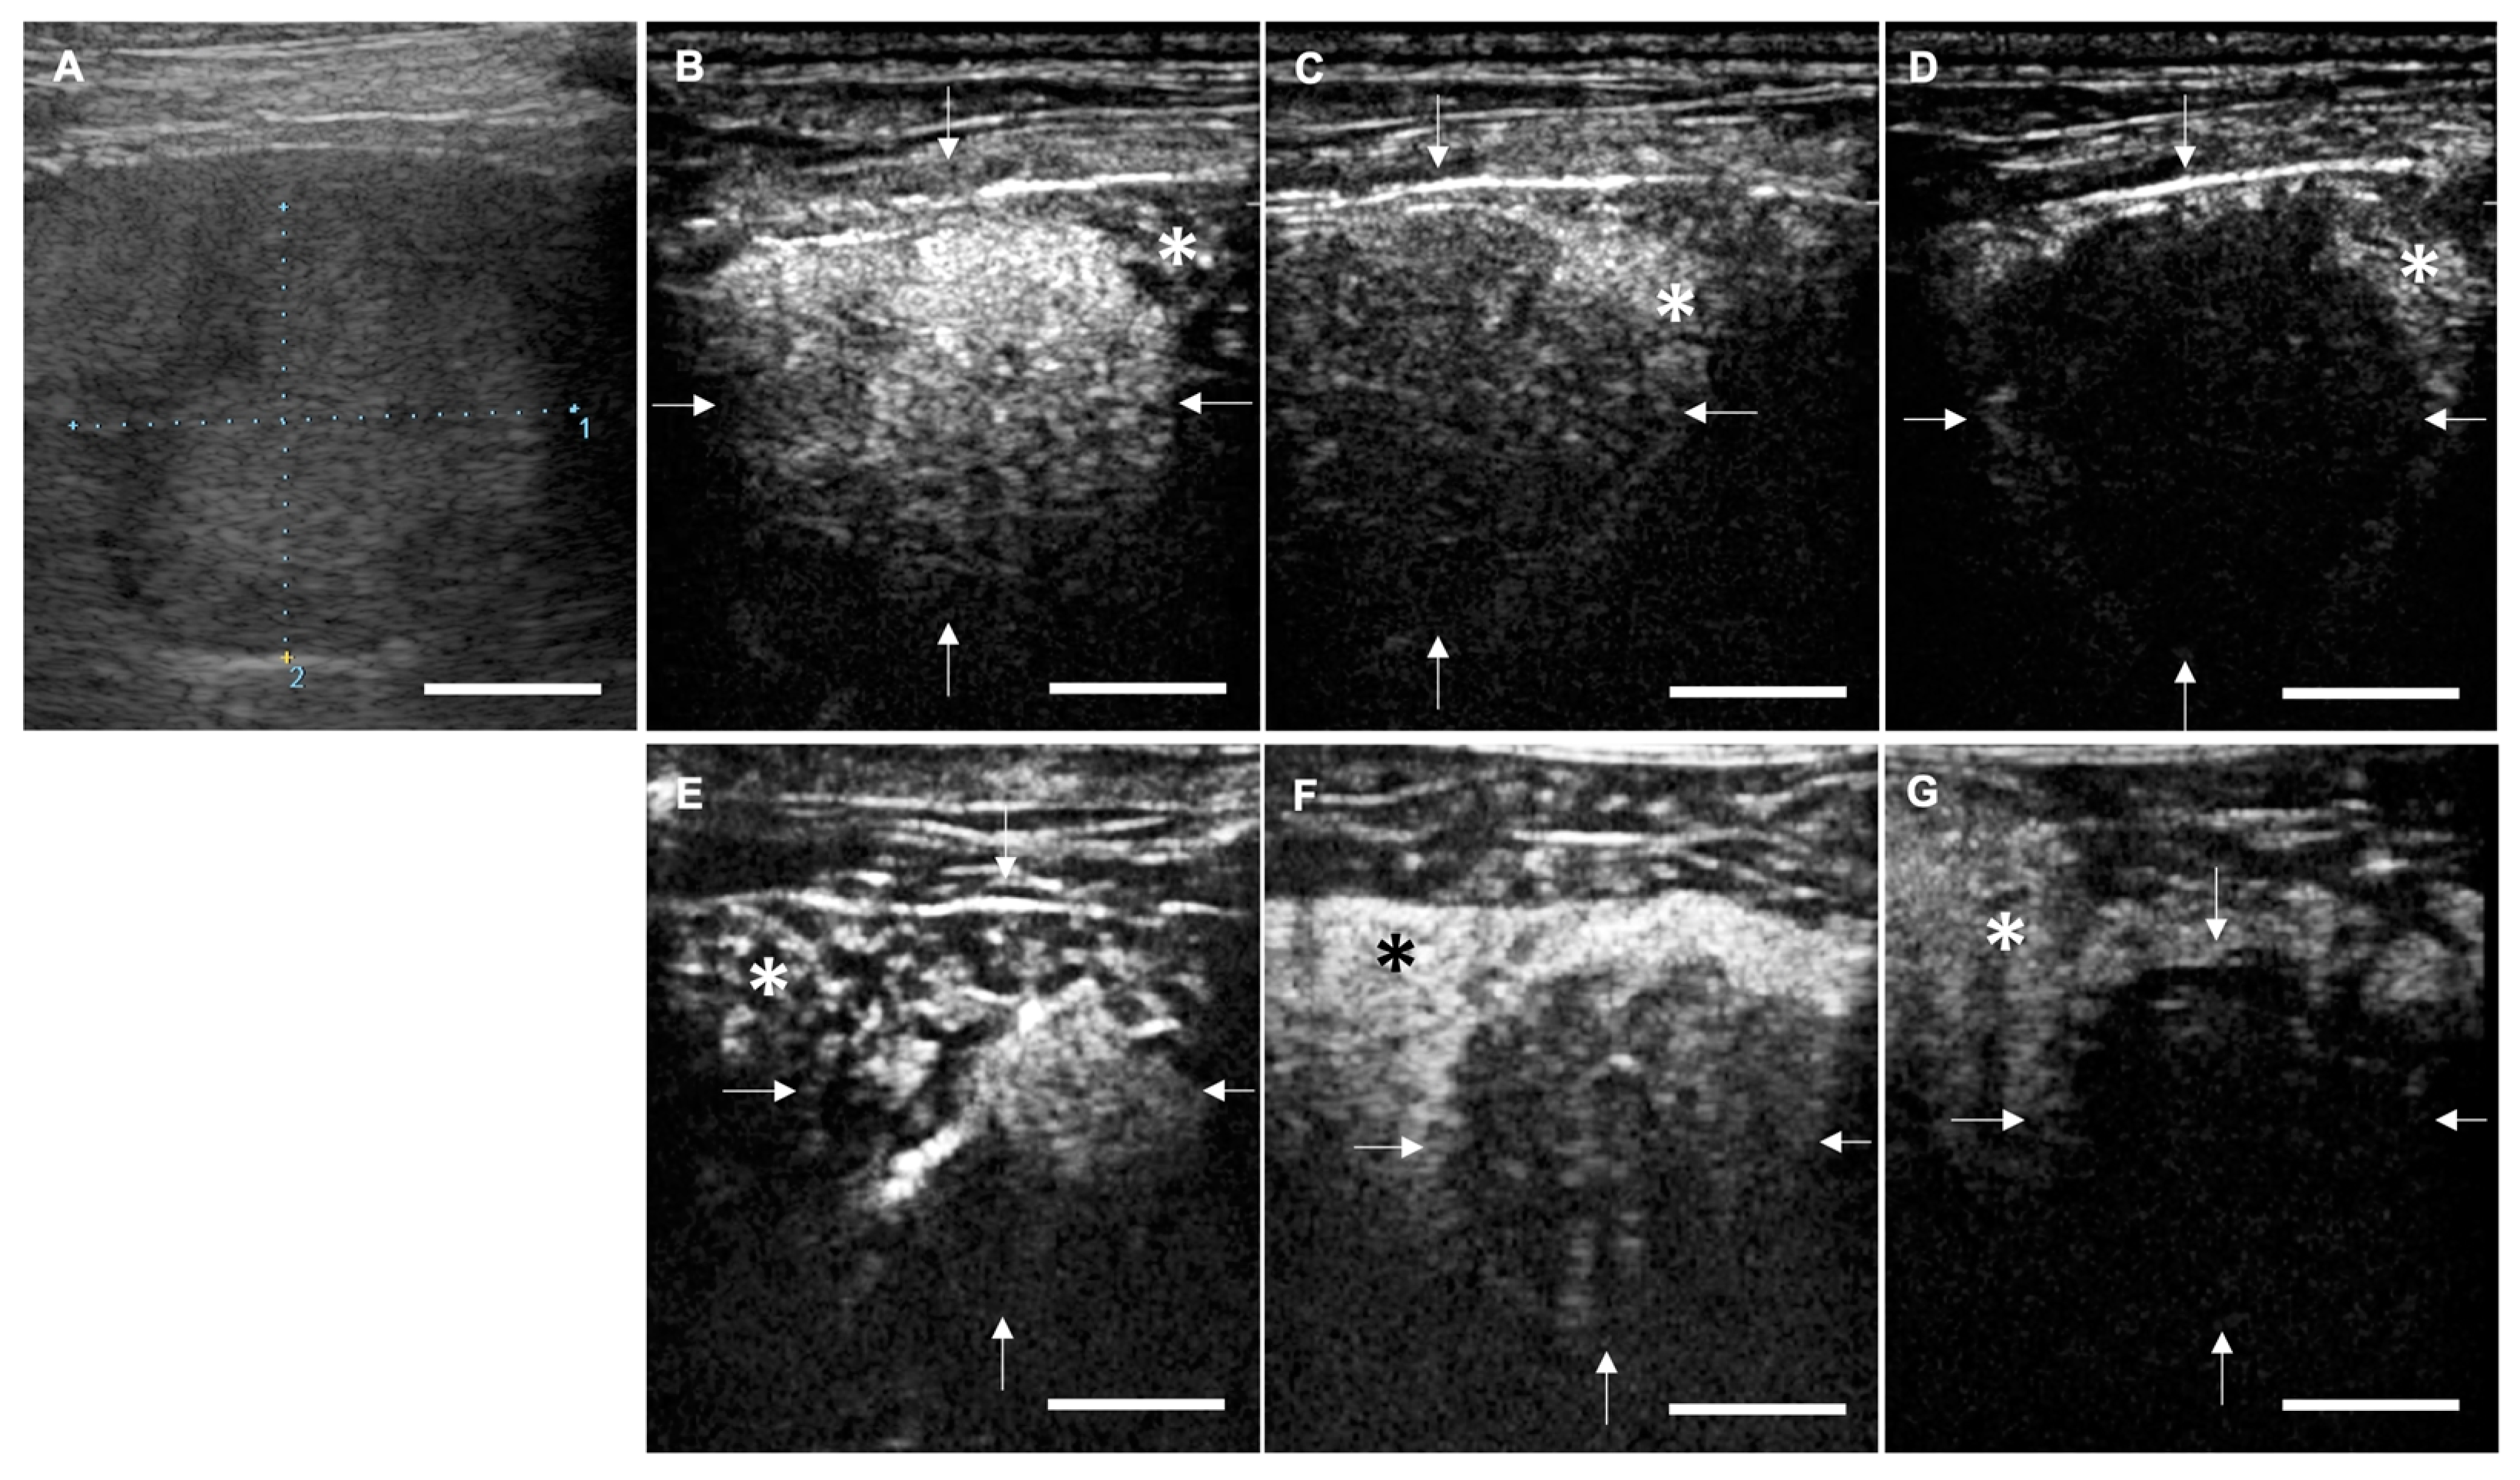

2.3. Anti-Tumor Effects of LBs in Combination with Therapeutic US and Liposomal Doxorubicin

4.4.1. Animals

4.4.2. Treatment Protocol

4.4.3. CEUS for the Assessment of Tumor Vasculature

4.4.4. Measurement of Tumor Size